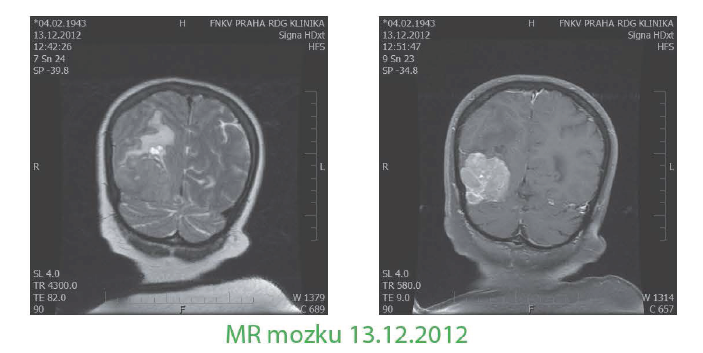

I. meta do CNS

- 11 /2012 psychické problémy, kognitivní deficit, levostranná hemiparéza - MRI mozku: expanzivně se chovající ložisko okcipitálně vpravo 40x51 x30mm s výrazným kolaterálním edémem pravé hemisféry, bez dalších známek generalizace, 14/12/2012 neurochirurgické makroskopicky radikální odstranění tumoru, histologie - metastáza malig.melanomu, mikroskopicky nebylo možné se vyjádřit k radikalitě, proto indikována paliativní RT - 7 /1 /2013-1 /2/2013 Co60 30Gy/1 Ofrakcí - celé kranium, 20Gy/Sfrakcí boo st na lůžko tumoru